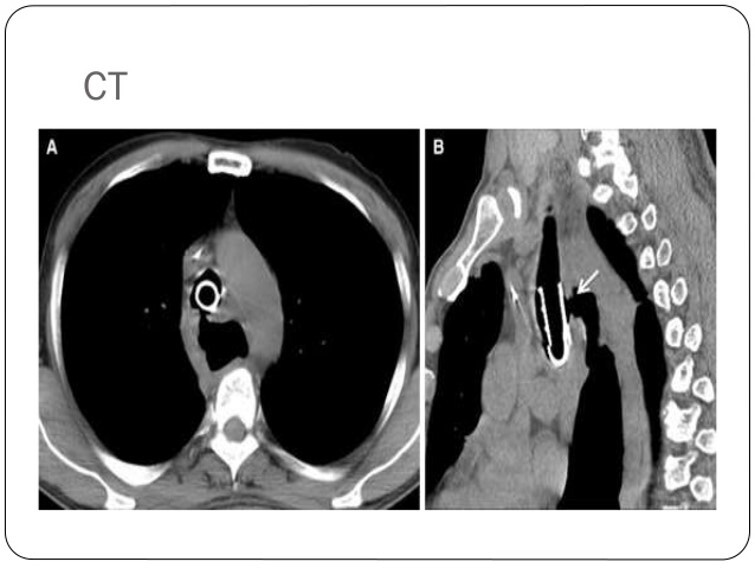

What pathology is seen here?

Tracheoesophageal Fistula

What are the radiographic signs of a Tracheoesophageal Fistula?

-Connection of the fistula between airway and esophagus

-Large dilation of the esophagus